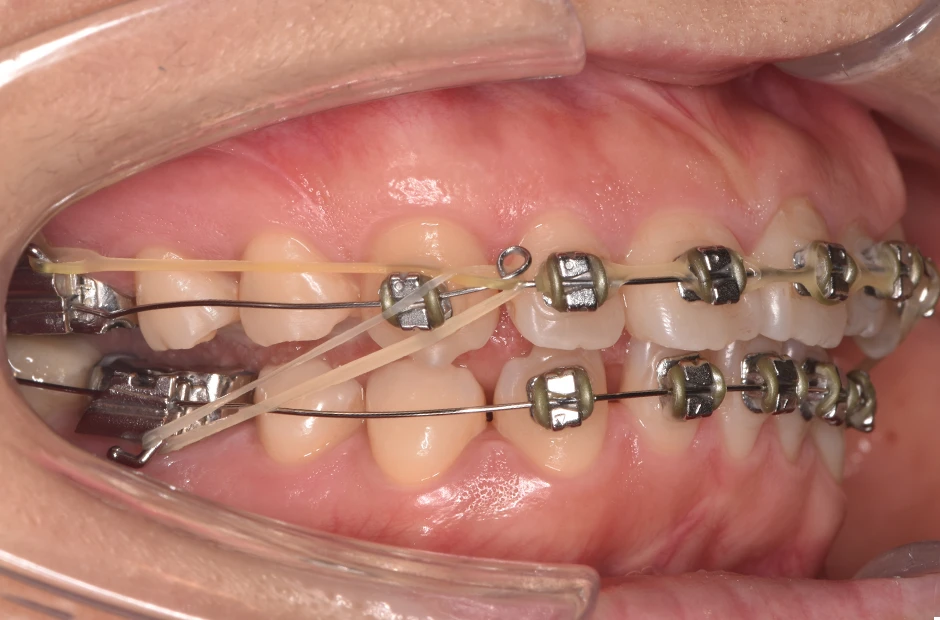

反対咬合

| 診断名・主訴 | 下顎前突、叢生 |

| 年齢・性別 | 23歳・女性 |

| 治療期間・回数 | 3年 |

| 治療に用いた主な装置 | 上顎5,5 下顎4,4 |

| 抜歯部位 | 舌側矯正 |

| 治療費 | 100万円(税抜) |

| リスク・副作用 | 装置による違和感・疼痛・歯肉退縮・歯根吸収・虫歯のリスクなど |

治療中